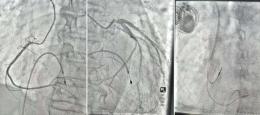

西安医学院三附院高难度封堵术让六旬患者告别反复头晕头痛

阳光讯(记者 郑亚雷)“折磨人十年的头晕头痛终于好了!现在脑袋清清爽爽,太感谢吕安林院长和他的团队了!” 67岁的方先生来自山西,脸上洋溢着久违的轻松笑容。困扰他十年的反复头痛、头昏症状,在西安医学院...